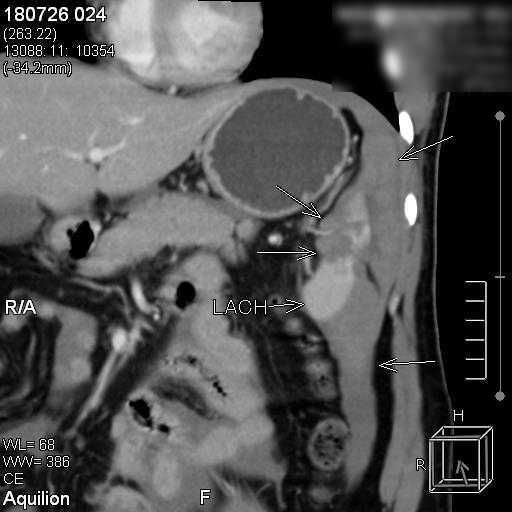

Suýt chết vì vỡ lách sau tai nạn giao thông dù không chảy máu ảnh 1hình ảnh động mạch lách của bệnh nhân

Bác sĩ CKII Nguyễn Phước Thuyết – Trưởng khoa Chẩn đoán hình ảnh, Bệnh viện Hoàn Mỹ Sài Gòn trực tiếp thực hiện, bằng cách luồn ống thông nhỏ từ động mạch đùi thông qua động mạch chậu vào động mạch chủ và đến động mạch lách.  Tại đây, Bác sĩ sẽ bơm thuốc cản quang nhằm xác định vị trí động mạch lách bị vỡ. Bác sĩ sẽ tiếp tục luồng một ống siêu nhỏ vào động mạch đang chảy máu và bơm keo vá chỗ thủng, giúp cầm máu và gắn liền nhu mô lách. Từ đó, truyền thuốc tắc mạch vào vị trí bị vỡ giúp tìnhtrạng chảy máu tại lá lách được kiểm soát.